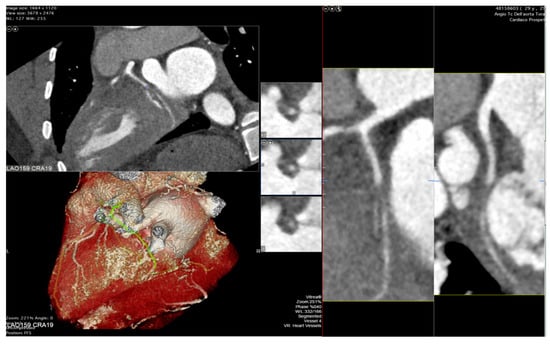

The integration of intravascular ultrasound (IVUS) with ICA reveals approximately 19% more cases of CAV, making it the most sensitive test available for monitoring CAV progression in the clinical setting [55]. However, CCTA has been proposed as an alternative to IVUS for routine follow-up of HT patients due to its superior spatial resolution [56]. In a recent meta-analysis, the sensitivity, specificity, positive predictive value, and negative predictive value of CCTA for detecting CAV were reported as 97%, 81%, 78%, and 97%, respectively [57]. Nevertheless, there is currently no standard method available for the assessment of CAV on CCTA images, and distinguishing CAV from atherosclerotic lesions can be challenging (examples in Figure 2 and Figure 3).

Figure 3. Cardiac computed tomography images showing cardiac allograft vasculopathy grade IV-A according to the International Society for Heart and Lung Classification with a non-calcific, sub occlusive coronary plaque at the second tract of the circumflex coronary artery assessed with cardiac tomography angiography.